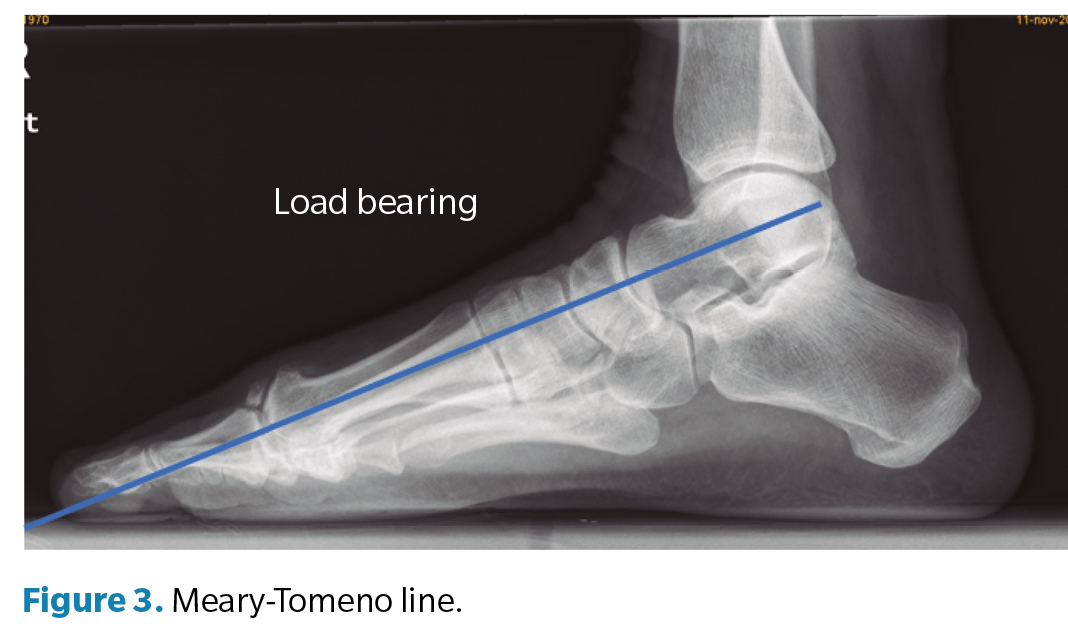

Regarding the goniometric variables in the lateral X-ray, the following angles were obtained: first metatarsal inclination angle, calcaneal inclination angle, Meary-Tomeno line, and internal Costa Bartani angle. The metatarsal inclination angle or Fick angle involves the inclination of the 5 metatarsals; however, for this study, only the inclination angle of the first metatarsal was considered (Figure 1), which was defined by the diaphyseal axis of the first metatarsal with the horizontal plane of the ground support11. The calcaneal inclination angle (Figure 2) is defined by the axis of the calcaneus, a line connecting the calcaneal tuberosity to the plantar margin of the anterior extension of the calcaneus near the calcaneocuboid joint, and the support plane (line formed by the proximal plantar tuberosity of the calcaneus and the head of the 5th metatarsal). A value of 20° is considered normal(12). The Meary-Tomeno line (Figure 3) is defined as the line passing through the axis of the talus (bisector of the angle formed by the tangent to the superior and inferior borders of the talus) and the axis of the diaphysis of the first metatarsal13). The internal Costa Bartani angle (Figure 4) is defined as the union of 3 points: the lowest point of the medial sesamoid, the lowest point of the posterior tuberosity of the calcaneus, and the lowest point of the talonavicular joint(14)..